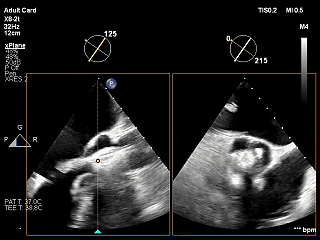

术前超声评估

经胸超声报告提示:患者二尖瓣2区及3区前叶关闭时脱入左房,二尖瓣重度反流(MR 4+),患者LA前后径约52mm,LVEDD约68mm,LVESD约42mm,EF值:65%,经胸超声测二尖瓣瓣口面积约6.1cm2,主动脉瓣无冠瓣脱垂并中重度反流,三尖瓣中度反流,估测中度肺动脉高压。

经食道超声精细化测量:肺静脉逆流,房间隔可穿刺高度约4.2cm,Flail宽度约21mm,Flail高度约8mm,Flail Gap约4mm, 3区AML长约23mm、PML长约12mm、2区AML约32.2mm,PML约16mm。

Bicomm切面看2区脱垂

上Color,可见反流主要来自于3区

X-Plane切面切1区未见明显异常

1区上Color,未见反流来源

X-Plane切面切2区可见前叶Flail

2区上Color,可见反流来源

X-Plane切面切3区可见前叶脱垂

3区上Color,可见反流来源

3D Enface 2区及3区前叶脱向左房

3D Enface 可见反流由2区3区从前后冲出

房间隔可穿刺高度约4.2cm

Flail宽度约21mm,Flail高度约8mm

经胸短轴测得瓣口面积约6.1cm2

3区前叶长度约22mm,后叶长度约11.6mm

2区前叶长度约32.2mm,后叶长度约16mm

2区Flail Gap约4mm